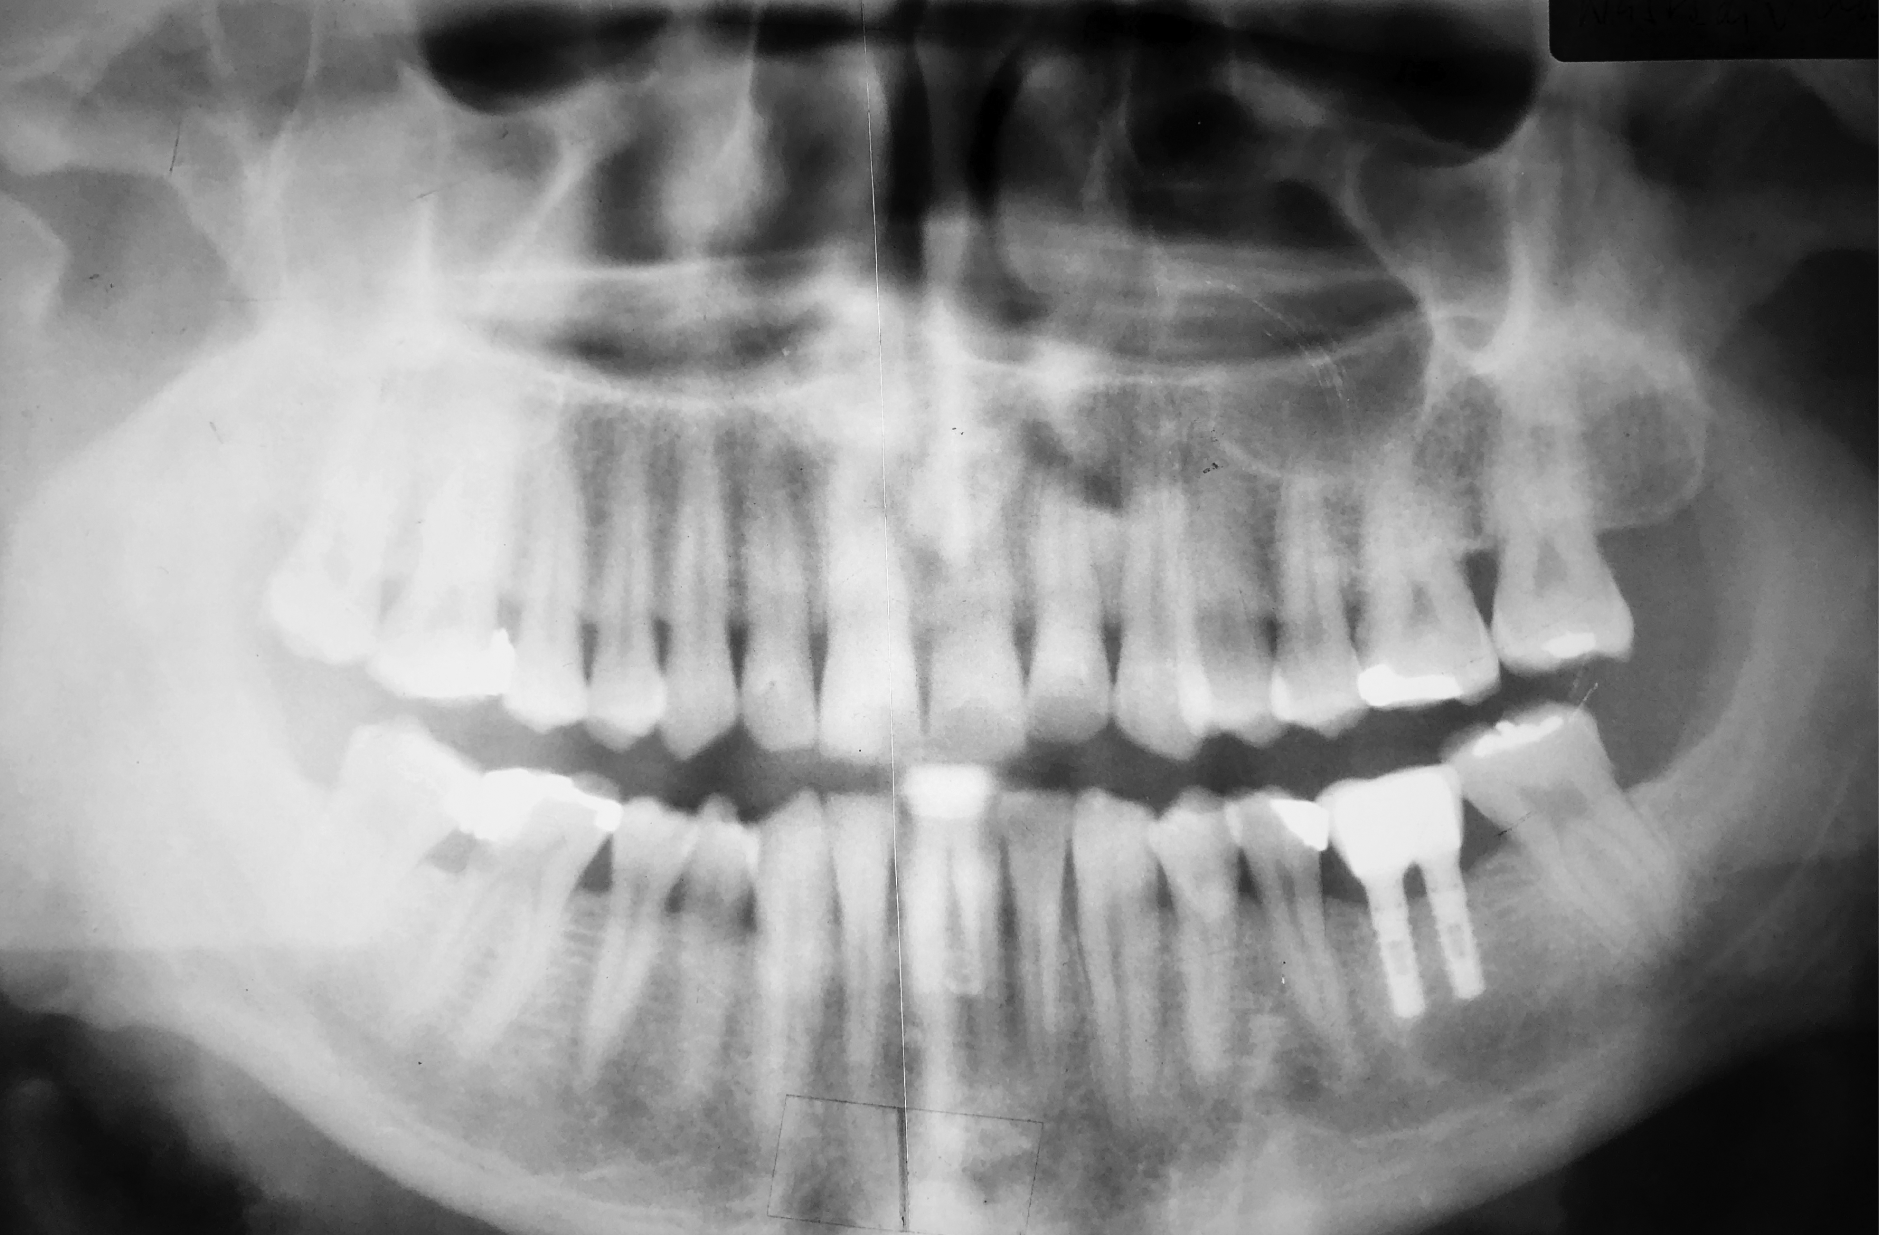

At the 21-year recall in March 2024, a follow-up X-ray confirmed implant stability with an unremarkable clinical presentation. No peri-implant bone resorption was detected over the entire period (0 mm).